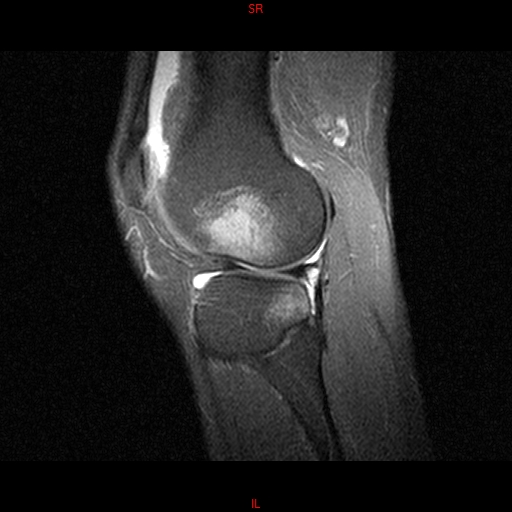

• Resonancia PATOLÓGICA MENISCOPATIA INTERNA DP SAGITAL

• Resonancia NORMAL RODILLA SAG DENSIDAD PROTONICA

• Resonancia NORMAL RODILLA SAG T1